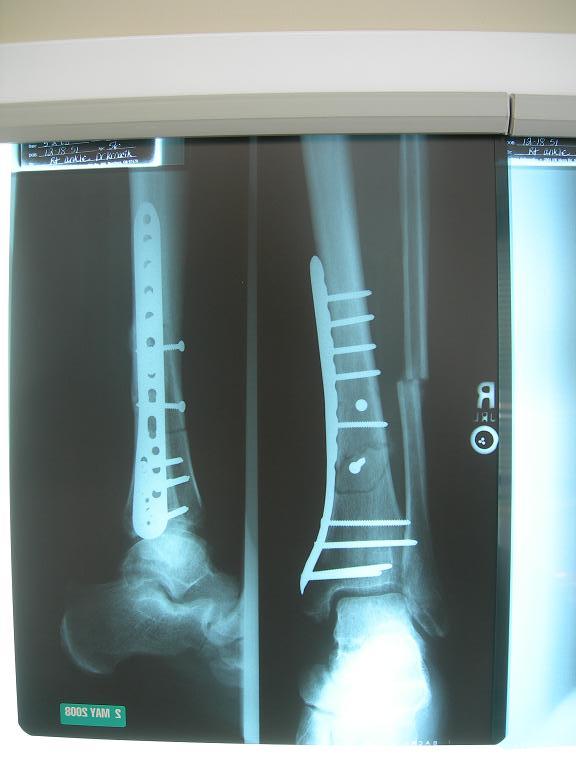

here's what it looked like after,, $60k

went in yesterday

now walking on it

with lots of swelling.

Damn blowhard, that's a lot of metal!

you'd think for the $

he'd snip off the ends sticking out ?

of my shin guard

Yikes Blowhard! That fibular doesn't look connected to the shinbone

That's whut I said, G-Man

but he seemed happy with it

"about 50% connected" he said

only 5% of my weight is on the fibula